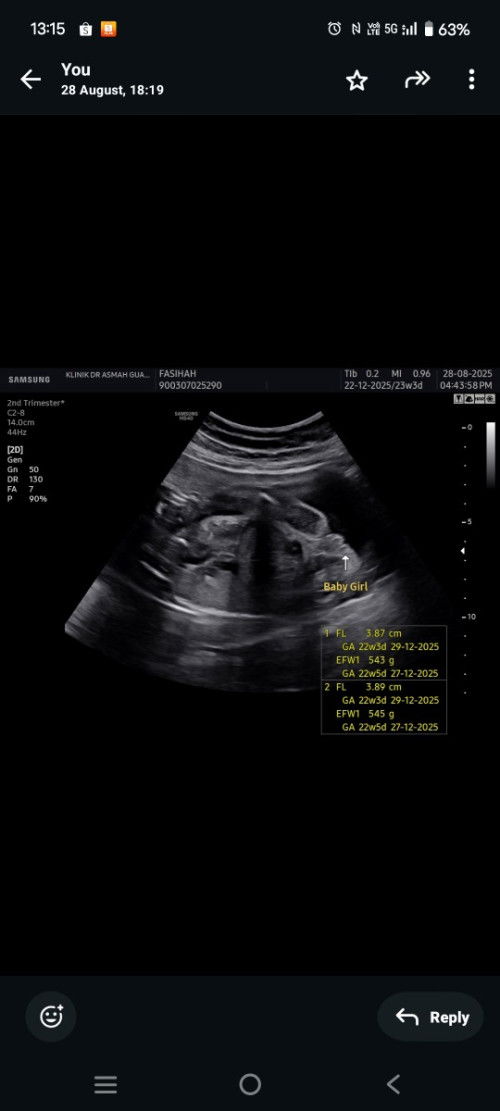

Scan gender 16 week

Sya Nti scan 21 week harap Baby girl Tpi xkisah la jnji Baby sihat dlm n mudah bersalin biasa Baby boy awal nmpk ade scan kt kk Tpi dr ckp xnmpk gender maybe sbb girl hehe harap lah